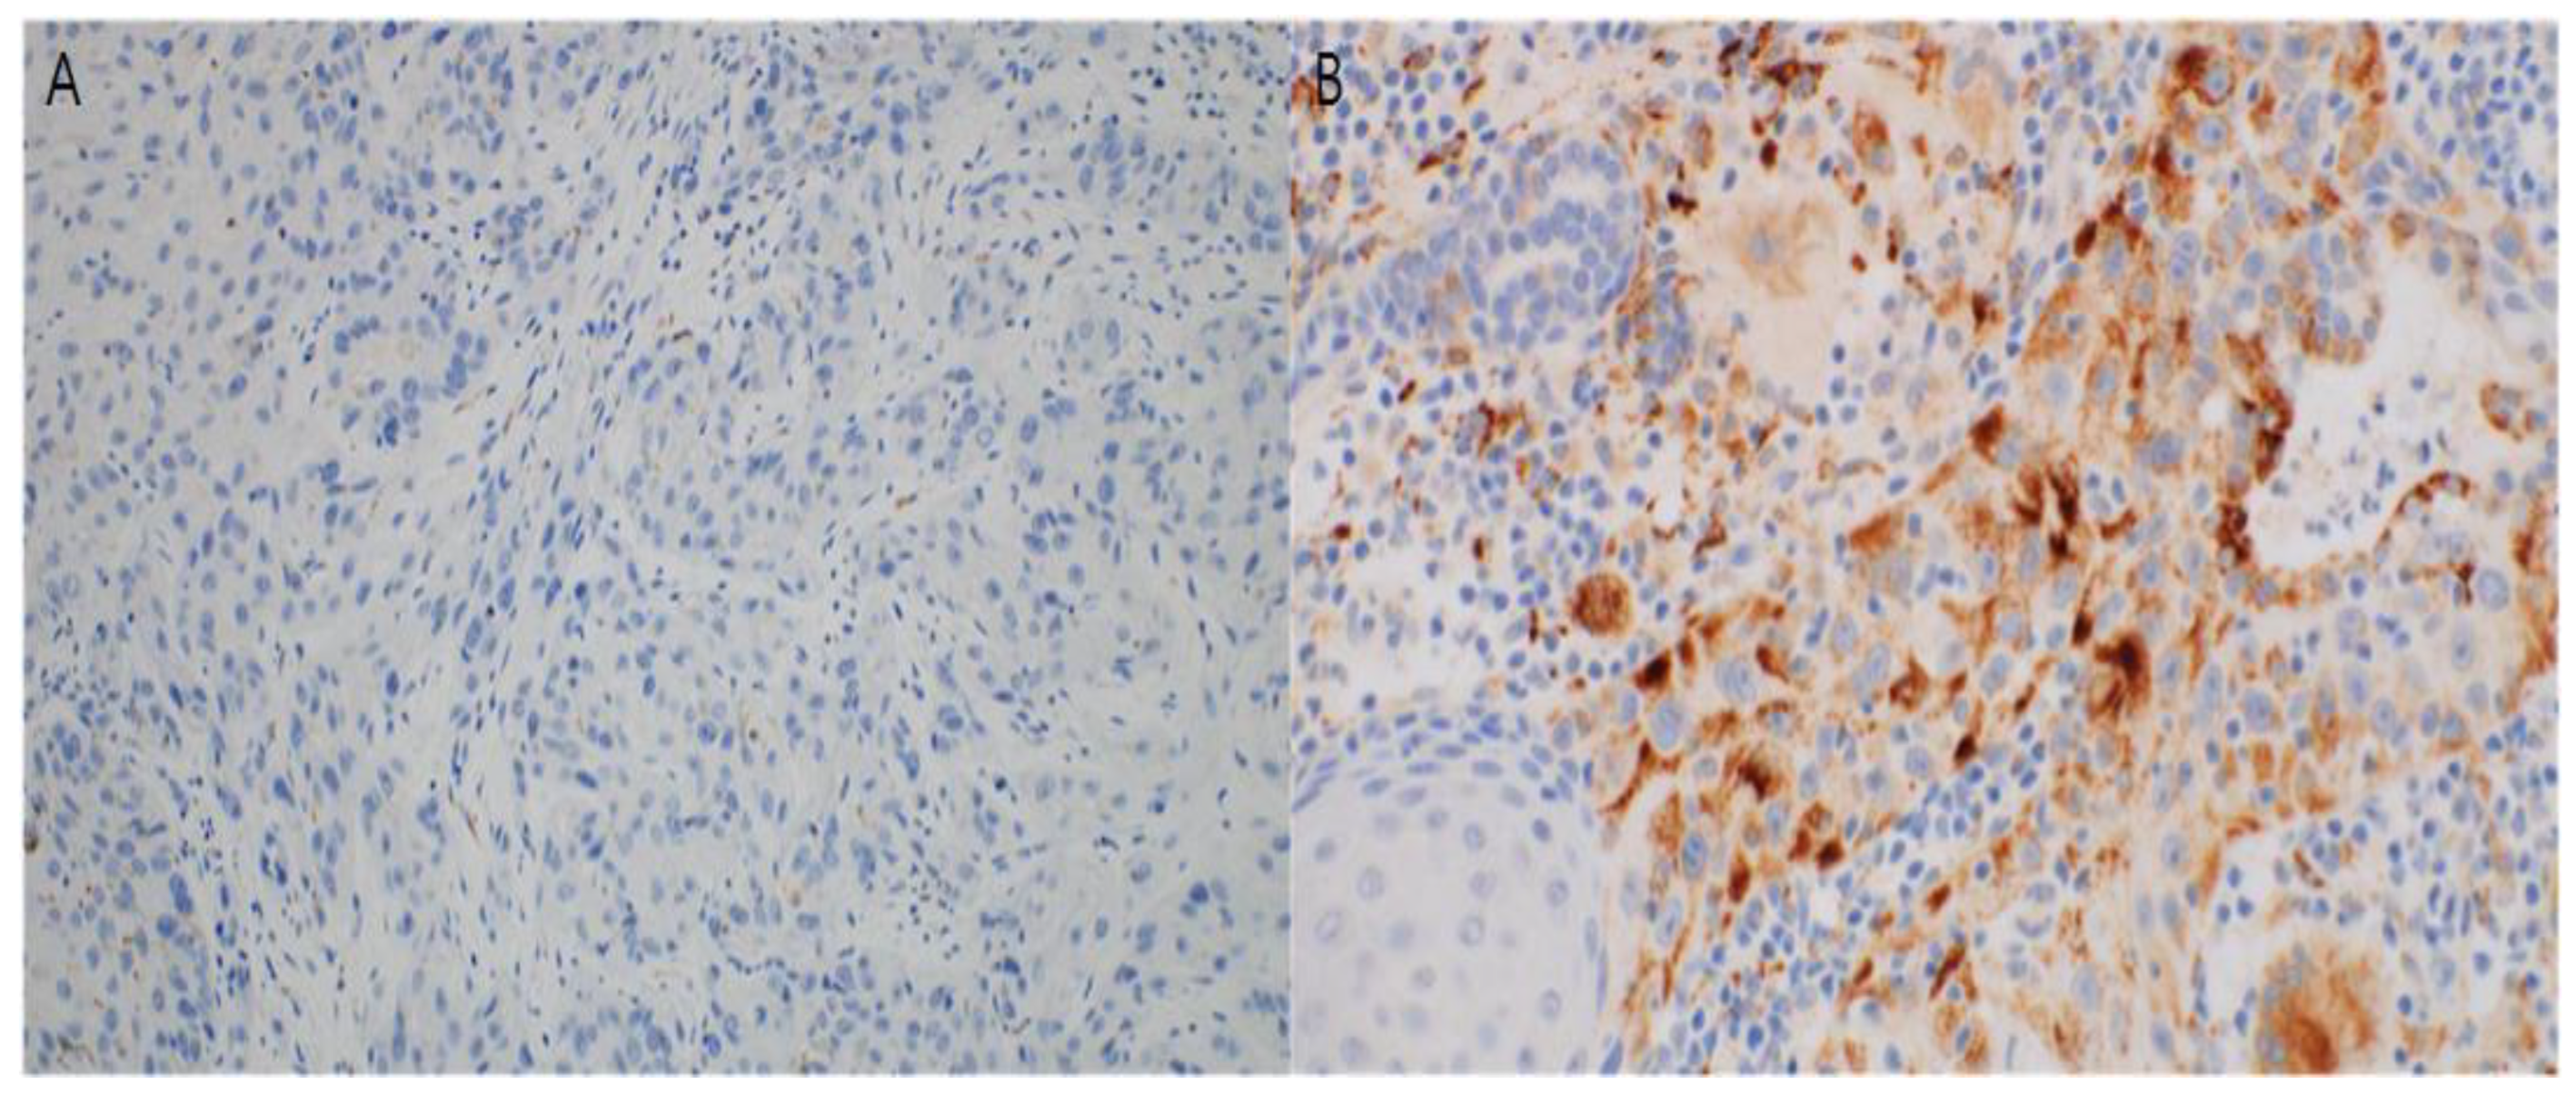

2.4. Immunohistochemistry and Interpretation

3.3. Immunohistochemical Study